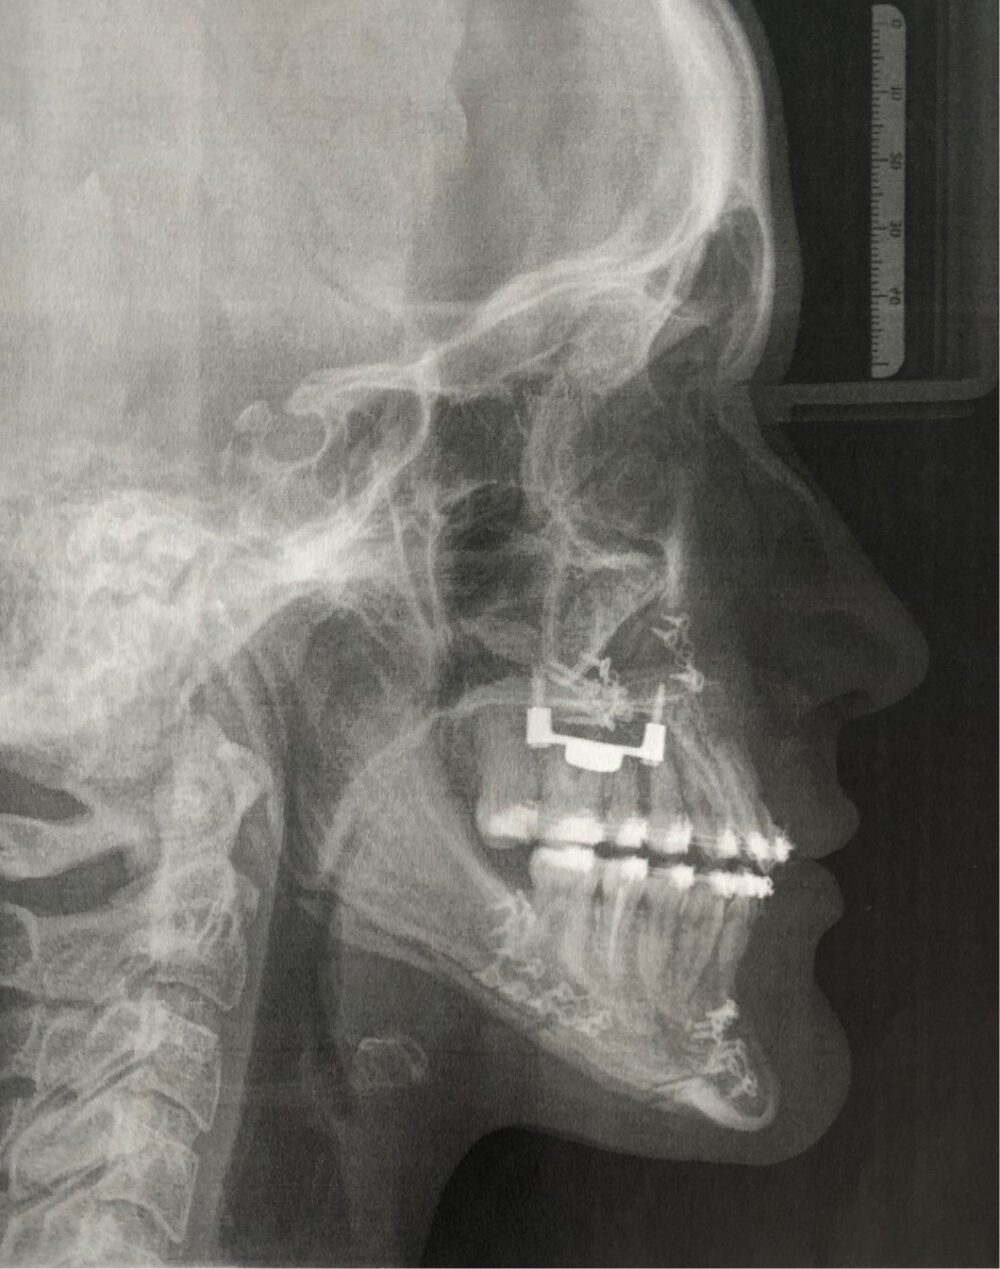

Therapie:

Surgery First: Bignathe Umstellungsosteotomie (Minimalinvasive Le Fort I Osteotomie mit Vorverlagerung und simultaner Oberkieferdistraktion, gesonderte Spina Nasalis Osteotomie zur besseren Kontrolle von Oberlippenposition und -volumen, Anhebung der Nasenspitze, Unterkiefersegmentosteotomie 32-42 zur Vergrößerung der sagittalen Stufe (Dekompensation),

Kinnosteotomie, Side Wing Osteotomie mit Beckenkamminterponat)